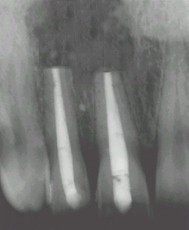

Les deux incisives présentent Traitement des canaux -resection 6 mois après-la radio se densifie

un kyste apicale-kyste enlevé -tache noire la tache est moins noire l'os se

correspondant au vide osseux reconstitue -guérison

L'os quant à lui,se reconstituera en 6 mois environ,une radio de contrôle permettra de visualiser cette guérison et reconstruction ,car l'image radio claire du granulome aura laissé la place à une radio parfaitement normale avec une densification osseuse notoire.Les travaux prothètiques pourront commencer si le besoin s'en fait sentir.